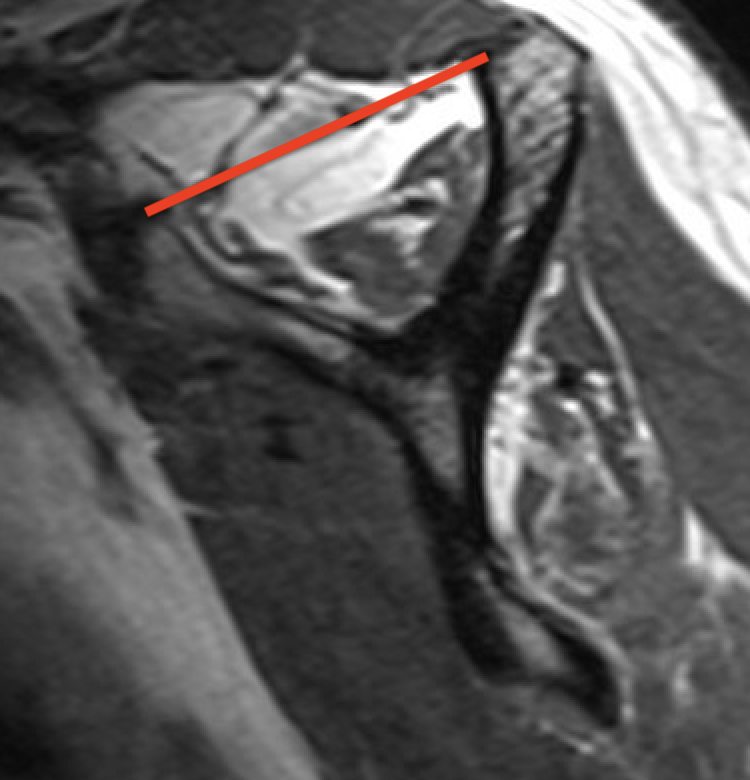

Supraspinatus atrophy

Tangent sign

- sagittal MRI

- line connecting superior coracoid and superior border scapular spine

- if supraspinatus muscle is below line, there is significant atrophy

- positive tangent sign / significant atrophy associated with larger tears / irrepairable tears

Negative tangent / no atrophy Positive tangent / significant supraspinatus atrophy